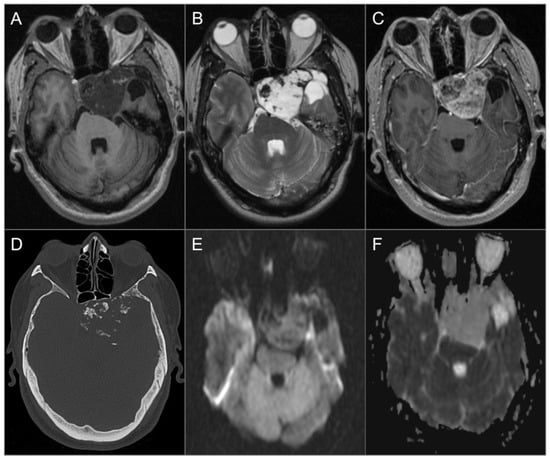

4.4.1. Chordoma

4.4.2. Chondrosarcoma